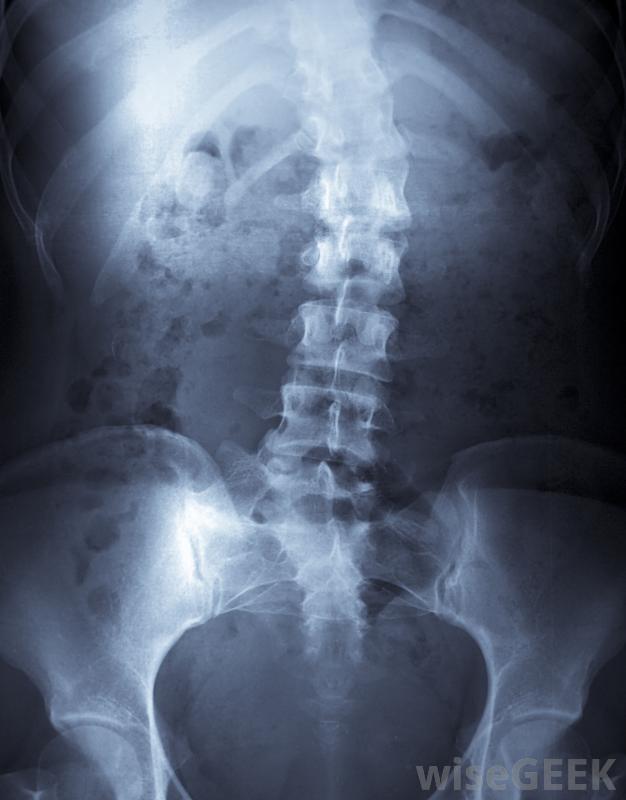

什么是身體支撐(Body Brace)?

身體支撐架是背部嚴重受傷或脊柱側凸等疾病患者佩戴的一種醫療器械,其作用是在脊柱愈合過程中,將脊柱的活動限制在一定范圍內,根據患者的需要,可以用硬的和軟的多種材料制成身體支架可用于治療脊柱側凸,這是脊椎的異常彎曲。要正確佩戴身體支撐,需要將幾個部位固定在正確的位置。下部圍繞著患者的骨盆區域,身體支撐的中間部分包裹著病人的腹部,身體支撐的上部固定在背部和肋骨上。可以佩戴身體支架來治療嚴重的背部損傷。支架的每個部分都類似于一個外殼。包裹背部的部分的外殼包含左右兩部分。支架的中心部分連接到支架通過兩個旋轉裝置卡入到位。上部各部分的獨立部分通過旋轉裝置固定在中間部分支架還有連接到上、下和中心部分的支架,以在佩戴過程中使設備保持在正確的位置。支架的設計和放置允許患者在使用支架時盡可能多地走動,而不會對脊柱造成損傷。雖然很少有人會說他們真正喜歡佩戴作為一個身體支撐物,替代品可能會對手術修復的脊柱造成足夠的傷害,以至于需要進行另一次痛苦而昂貴的手術,或者無法治療可能導致嚴重疼痛的醫療狀況。考慮到這些可能性,在必要的治療或恢復期間,幾乎不間斷地佩戴身體支撐架,這看起來并沒有那么糟糕。在許多情況下,身體支撐物都能起到作用。脊柱手術后,如脊柱融合術,支架可防止患者脊柱側凸,脊柱側凸是指脊柱向左或向右彎曲超過10°的一種情況,一個支架可以幫助脊柱正確對齊,并使身體得到適當的發育。戴一個身體支架可能是一個長期的前景,但是是暫時的。大多數人在手術后痊愈或脊柱對支撐治療有反應后,可以安全地取出支架。